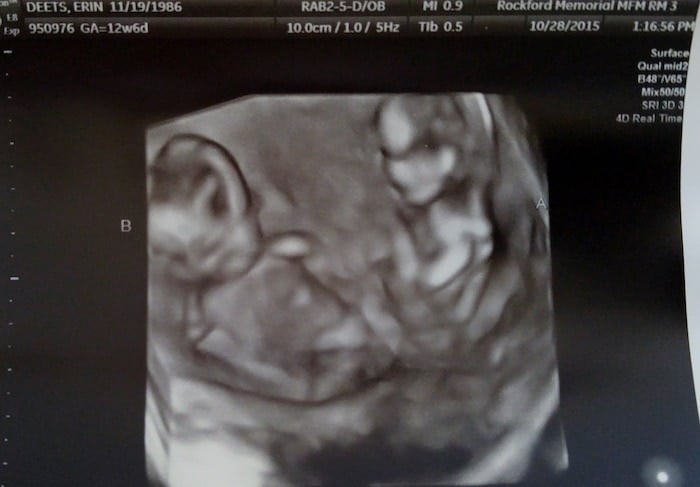

- Ultrasound Photos at 13 Weeks Pregnant With Twin

Ultrasound Photos at 13 Weeks Pregnant With Twin